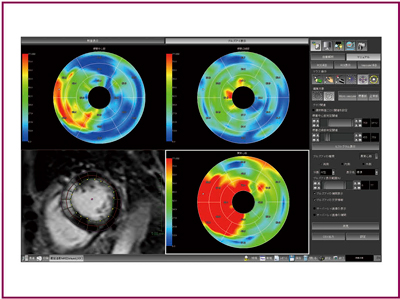

●MR遅延造影解析

現在,米国をはじめ,心臓領域におけるMRI検査の有用性が多くの医療機関で着目されている。当社も,AZE VirtualPlaceの開発当初からMRI心臓検査に注目し,これまでにMRIでの冠状動脈撮像画像(Whole Heart MRA)の3D表示やMRI心筋パフュージョンなど,多くのMRI心臓検査の解析機能を提供してきた。それらは2009年に行われた北米放射線学会(RSNA2009)の展示会場でも,多くの医療従事者から高い評価を得ている。中でも“MR遅延造影解析”(図5)は,新たな機能革新を遂げた。

ユーザーは,従来のように心筋のROIを手動で囲むことなく,自動ボタンをクリックするだけで,自動的に心筋ROIを設定することができる。また,梗塞部位を診断するために最も重要となる閾値設定は,画像の梗塞部位を囲むだけで,その信号値分布から自動的に閾値が設定される機能が実装された。もちろん,各施設で定められた固定値での閾値設定にも柔軟に対応できる。さらに,結果表示も梗塞領域をコア部分,グレー部分で分割表示することができ,その梗塞病変の緊急性などの性質診断をサポートする。

図5 MR遅延造影解析画面